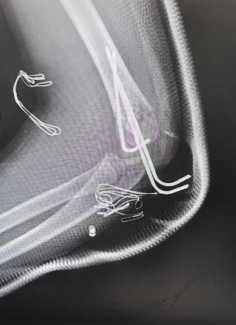

术后X线检查提示骨折复位效果佳

术后复查X线片显示,患儿骨折复位效果理想、对位对线良好,为患肘功能的顺利恢复筑牢基础。目前,在医护人员的专业指导与系统化康复计划的锻炼下,患儿正稳步恢复。家属对医院高效的救治流程、骨科团队高超的技术水平,以及全程温暖的医疗服务表达了由衷感谢。